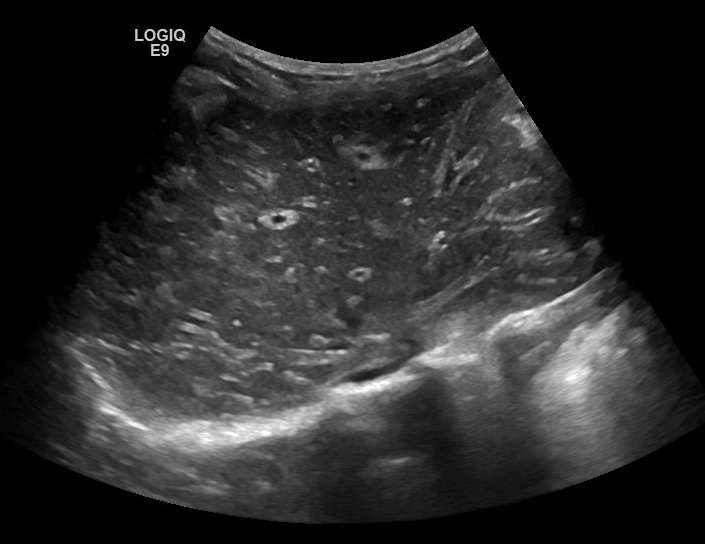

Cirrhosis